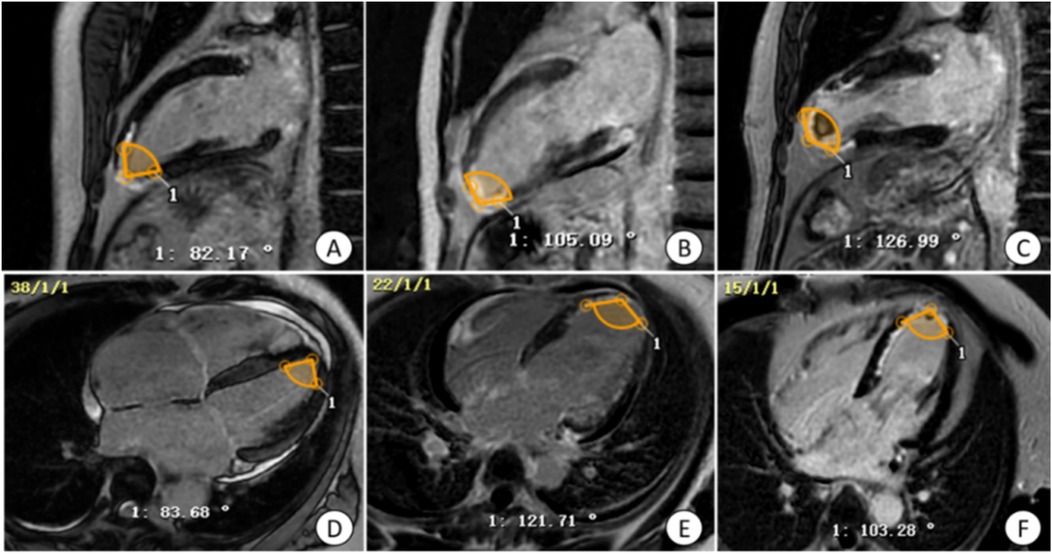

Figure 3

Operation plane of CVI42 software for measuring LGE area and gray area. (A) the operative plane on CVI42 software for measuring the LGE area and gray zone volume, and the area of enhancement in each segment can be represented by a 16-segment bull's-eye plot; (B) the short-axis (SA) level of a patient with acute extensive anterior myocardial infarction with early ventricular wall aneurysms; (C) the short-axis level of a patient with acute anterior myocardial infarction without early ventricular wall aneurysms, which was found to have a smaller LGE extent than the (B) image, with the light yellow area is the LGE area, tan area is the gray area, and blue area is the area of interest. LGE, late gadolinium enhancement.

2.2.2.4 LGE region and gray zone analysis

By selecting the tissue feature module in CVI42 software, combined with AI technology, the endocardium and epicardium of each image layer from the base to the apex were automatically outlined, and the normal myocardium was manually circled as the region of interest (ROI) with blue color in the same layer, and the regions with a signal intensity greater than that of the normal myocardium by 5 times the standard deviation and above were selected and identified as LGE regions, and the gray zone analysis option was checked, and finally the mass and volume of LGE region and gray zone were automatically calculated. Check the gray area analysis option, select the area with 3 times standard deviation to be identified as gray area, and finally, the mass and volume of LGE area and gray area are automatically calculated (Figure 3).